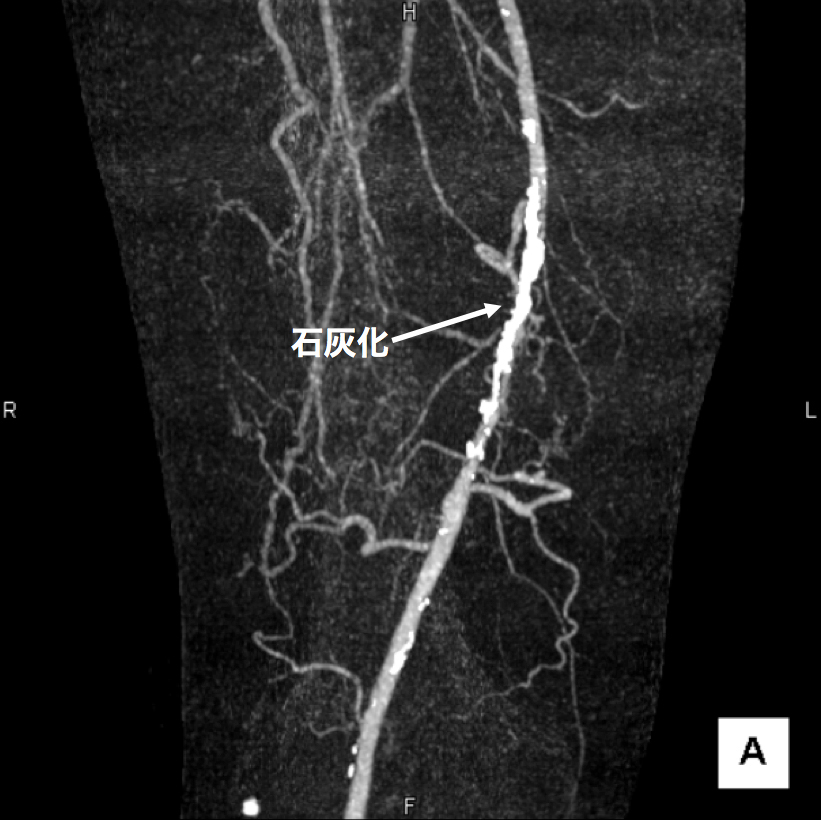

3、造影CT検査 造影剤を点滴しながらCTを撮像することで、血液の流れ、血管の状態などを把握します。情報量が多く治療方針を決定する場合に役立つので当院では特に力を入れている検査です。(図2、3、4)

【図3】下肢造影CT検査 この画像は血管の立体的な走行の把握に有用です。 右足大腿部の血管に強い石灰化(動脈硬化の変化)があります。